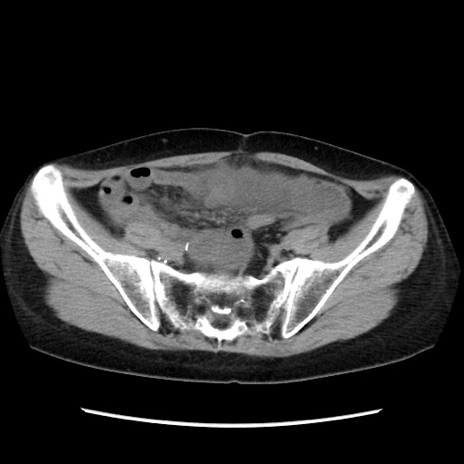

症例32(横断像)

【症例】40歳代 女性

【主訴】上腹部痛、嘔気・嘔吐

【現病歴】約9時間前頃から急に上腹部痛、嘔気、嘔吐が出現。改善しないため救急要請。

【既往歴】子宮頚癌(広汎子宮全摘術、放射線療法)、腸閉塞

【身体所見】腹部:平坦、軟、腸雑音亢進、上腹部を中心に腹部全体に圧痛あり。

【データ】WBC 8400、CRP 0.03